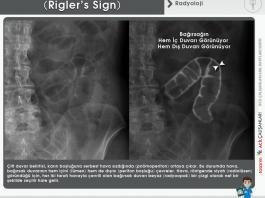

Ana Sayfa Radyoloji Direkt Batın Grafisi Değerlendirilmesi

Direkt Batın Grafisi Değerlendirilmesi